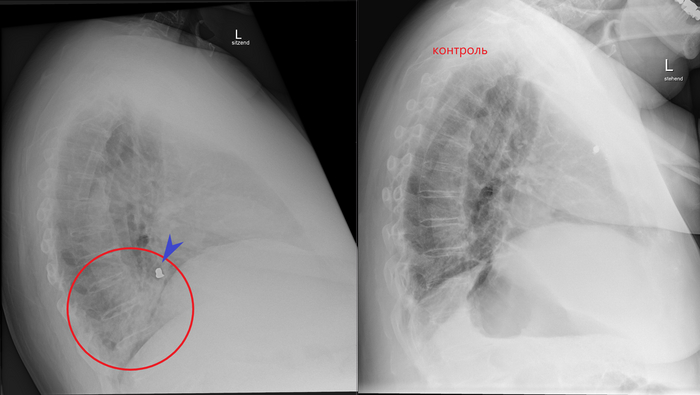

Контрольный снимок через пару месяцев после удаления пломбы из просвета бронха показывает отсутствие инородных тел в проекции воздуховодных путей, а также практически полное "рассасывание" пневмонии: